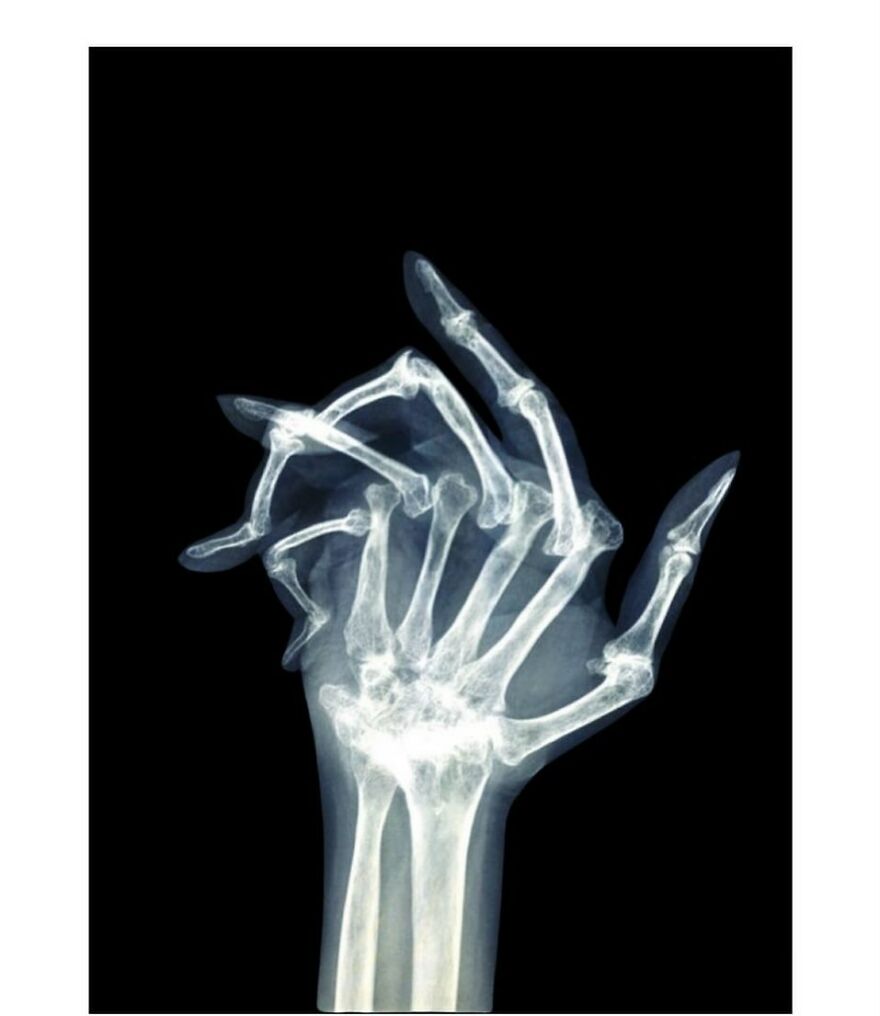

Plain radiograph of wrist joint shows polydactyly with duplication of ulna, duplication of ulnar side of carpal bones, metacarpals and phalanges, absence of radius and absence of thumb. Eight triphalangeal digits are seen. The middle phalanx of medial index finger is hypoplastic